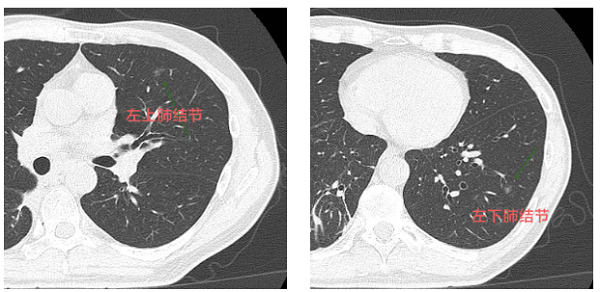

原來(lái),韋先生在每年的例行檢查中,發(fā)現(xiàn)了雙肺多個(gè)高危磨玻璃結(jié)節(jié),柳州市人民醫(yī)院健康管理中心立即給韋先生安排了院內(nèi)就診。完成第一階段右肺治療后,左肺的兩枚高危結(jié)節(jié)亟待解決。

若采用傳統(tǒng)手術(shù),需要切除左肺較多肺組織,這就好比在拆除“炸彈”時(shí),不小心把周?chē)摹昂梅孔印币膊鹆艘淮笃瑒?chuàng)傷大、恢復(fù)慢,術(shù)后生活質(zhì)量也會(huì)大打折扣。

韋先生的“掃雷”行動(dòng)需要制定一份詳細(xì)的“作戰(zhàn)計(jì)劃。醫(yī)院胸外科主任曹健斌主任醫(yī)師帶領(lǐng)多學(xué)科診療(MDT)團(tuán)隊(duì)進(jìn)行了深入評(píng)估。胸外科、腫瘤內(nèi)科、醫(yī)學(xué)影像科、麻醉科專(zhuān)家為患者制定了“一站式”雜交手術(shù)方案通過(guò)一次手術(shù),同時(shí)處理肺部深處和淺表的多發(fā)結(jié)節(jié),盡可能保留健康的肺組織,幫助患者術(shù)后更快康復(fù)